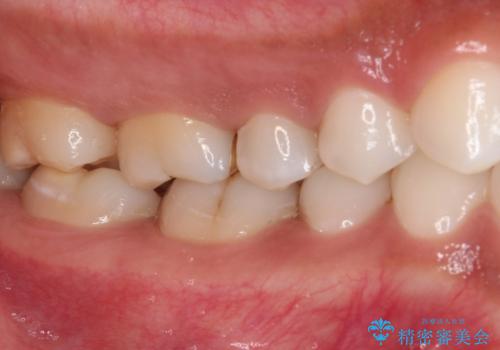

奥歯のむし歯をゴールドインレーで修復

奥で目立たないことから、虫歯の再発リスクが最も低く、咬合力による歯への負担も少ないゴールドインレー(PGAインレー、白金加金インレー)にて修復治療をすることとしました。

ゴールドインレーは銀歯のインレーやセラミックインレーと比べ、「技工操作の精度が高く、適合が著しく良い」というメリットがあります。特に上の奥歯は歯科医師の操作が行いにくいため、「適合の良さ」は再治療のリスクを防ぐ上でとても重要な要素となります。

上の奥歯は金属色が見えることもないため、審美的な問題は全くありません。

咬み心地はとても良好で、全く違和感がなく、患者様には大変満足していただきました。